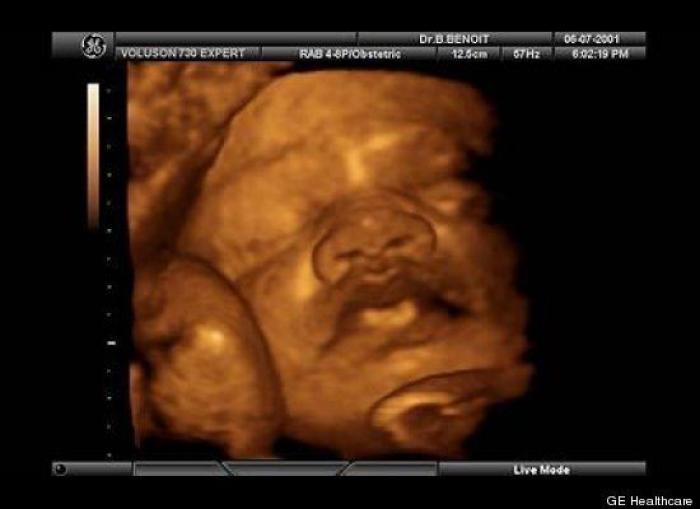

En esta galería puedes ver en fotos como es el desarrollo de un feto de semana en semana:

Desarrollo del feto, en fotos